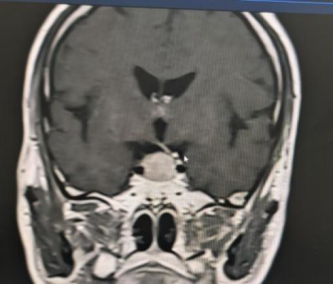

患者为69岁男性,因持续性头痛、视力下降伴双眼颞侧视野缺损前往阆中市人民医院神经外科就诊。经综合评估,结合内分泌检查及1.5T MRI动态增强扫描,确诊为垂体大腺瘤(2.0cm×1.7cm×1.7cm),肿瘤向上压迫视交叉,并伴有蝶窦气化不良。

针对该病例,垂体瘤多学科诊疗中心(MDT)多次组织讨论。鉴于传统开颅手术创伤大、恢复周期长,团队最终决定采用经鼻蝶内镜垂体瘤切除术。该微创技术通过鼻腔自然通道进入蝶鞍区切除肿瘤,具有创伤小、出血少、恢复快等优势。

手术过程中,团队在神经导航精准定位下,经鼻腔自然通道建立微创手术入路,完整切除肿瘤的同时最大限度保护正常组织结构,手术切口仅约2.0×1.5cm。术后患者恢复良好,无并发症发生,症状明显改善,目前已康复出院。